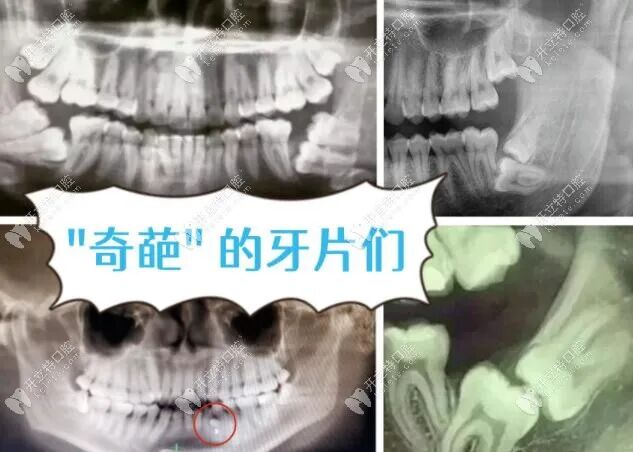

其实不仅要拍片,而且牙片有小牙片/全景片/头颅侧位片/CT呢,下面开¤¤ 立Ψ特※※小编就为大家详细介绍下口腔中的小牙片/全景片/头颅侧位片/CT区别,以及不同的牙片主要用在什么牙齿治疗上。

“拍牙片”只是一个统称,一般来说,我们所说的牙片由以下几种组成:小牙片、全景片头颅侧位片、牙科CT。

1、小牙片

也称为“根尖片”通常一张小牙片显示1-3颗牙齿,可以帮助牙医确定个别牙齿龋坏程度、炎症扩散范围、牙周骨头状况、隔壁牙齿情况等等。

2、全景片(曲面断层片)

顾名思义,全景片就是拍摄全口牙齿。拍摄范围较广,在一张全景片上可以同时看到全口牙、双侧上下颌、颞颌关节、上颌窦下颌神经管、牙槽骨等部位情况。

可以了解牙根下是否有囊肿,周围骨头是否吸收,牙槽骨内是否有埋伏牙、多生牙等。